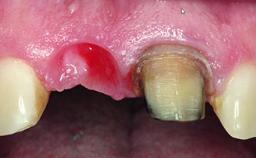

A healthy 37-year-old female patient was referred for a consultation on the replacement of missing tooth 21 with an implant-supported restoration. She stated that several years previously the tooth had been traumatically avulsed following a motor vehicle accident. The tooth was replaced with a three-unit fixed partial denture (FPD) immediately afterwards. Over time, she became disillusioned with the FPD and looked for a different option, including orthodontic therapy. She presented still in her orthodontic appliances, with the pontic sectioned free from the FPD but attached to the archwire. Her orthodontist felt that orthodontic treatment had been successfully completed, but nevertheless referred her before removing the appliances in case adjustments were necessary.

Bone Augmentation Horizontal|Simultaneous

Soft Tissue Grafting Simultaneous